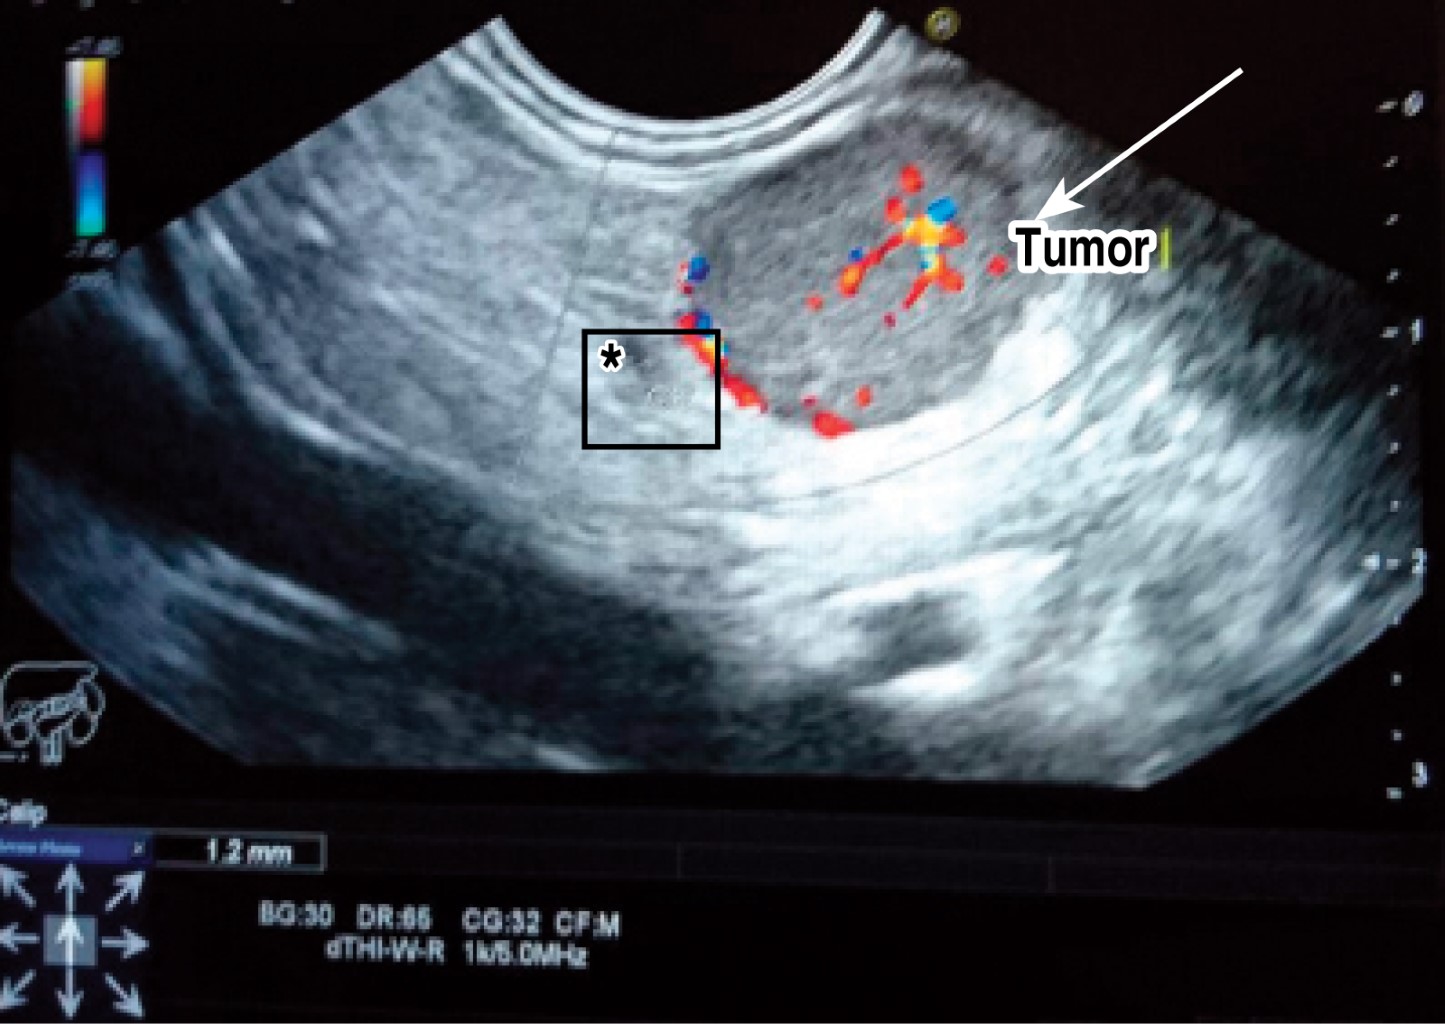

Se trata de un paciente femenino de 51 años de edad sin antecedentes familiares de importancia. Inicia con el padecimiento tres años previos a su ingreso al referir episodios intermitentes de diaforesis, palpitaciones, se valora con glicemia capilar en 28 mg/dl, presenta además cefalea de tipo opresiva de localización frontal, intensidad 5 de 10 en la escala visual análoga, mejora su sintomatología tras la administración de solución intravenosa o alimentos ricos en glucosa. Dos años después se presenta con crisis convulsiva por lo cual acude a valoración, a la exploración física: de edad aparente a la cronológica, tórax sin alteraciones, abdomen globoso a expensas de panículo adiposo, blando depresible no doloroso a la palpación, peristalsis presente y normal, el resto de la exploración sin datos patológicos. Sus estudios paraclínicos muestran hemoglobina glucosada en 4.5%, sulfonilureas en sangre negativas, glicemia de ingreso 37 mg, insulina en 64.1 UI/ml, péptido C en 8.36 ng/ml, TSH 1.8 UI/ml, T4L 1.11 ng/dl, los resultados de la tomografía axial computarizada (TAC) de abdomen contrastado se reportaron normales. En la resonancia magnética nuclear (RMN) aparece una lesión nodular entre la cabeza y el cuerpo del páncreas de 2.0 x 1.8 x 1.6 cm, la cual no condiciona obstrucción. Se procede a realizar ultrasonido endoscópico (Figura 1) corroborando la localización superficial del tumor, se encuentra a más de 2 mm de los vasos esplénicos y del conducto pancreático. Debido al tamaño y localización se procede a realizar enucleación laparoscópica del insulinoma. Se induce neumoperitoneo, se colocan puertos en cicatriz umbilical de 10 mm, otro puerto para el retractor hepático en línea anterior axilar derecha de 10 mm, dos puertos izquierdos y uno derecho de 5 mm. Se continúa con la disección del omento gastrocólico, se levanta la cámara gástrica y se observa la tumoración entre el cuello y cola del páncreas (Figura 2). Se realiza enucleación con bisturí armónico y se extrae de la cavidad abdominal con bolsa por el puerto del ayudante.

Figura 1